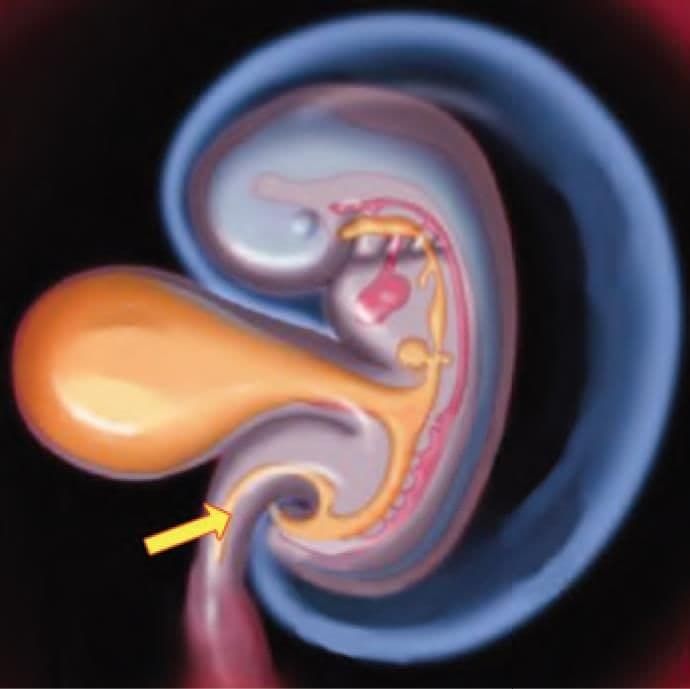

Adult derivative of the arrow marked structure in the following diagram is: (NEET-PG 2023)

Which of the following ligament develop in the arrow marked structure? (NEET-PG 2022)